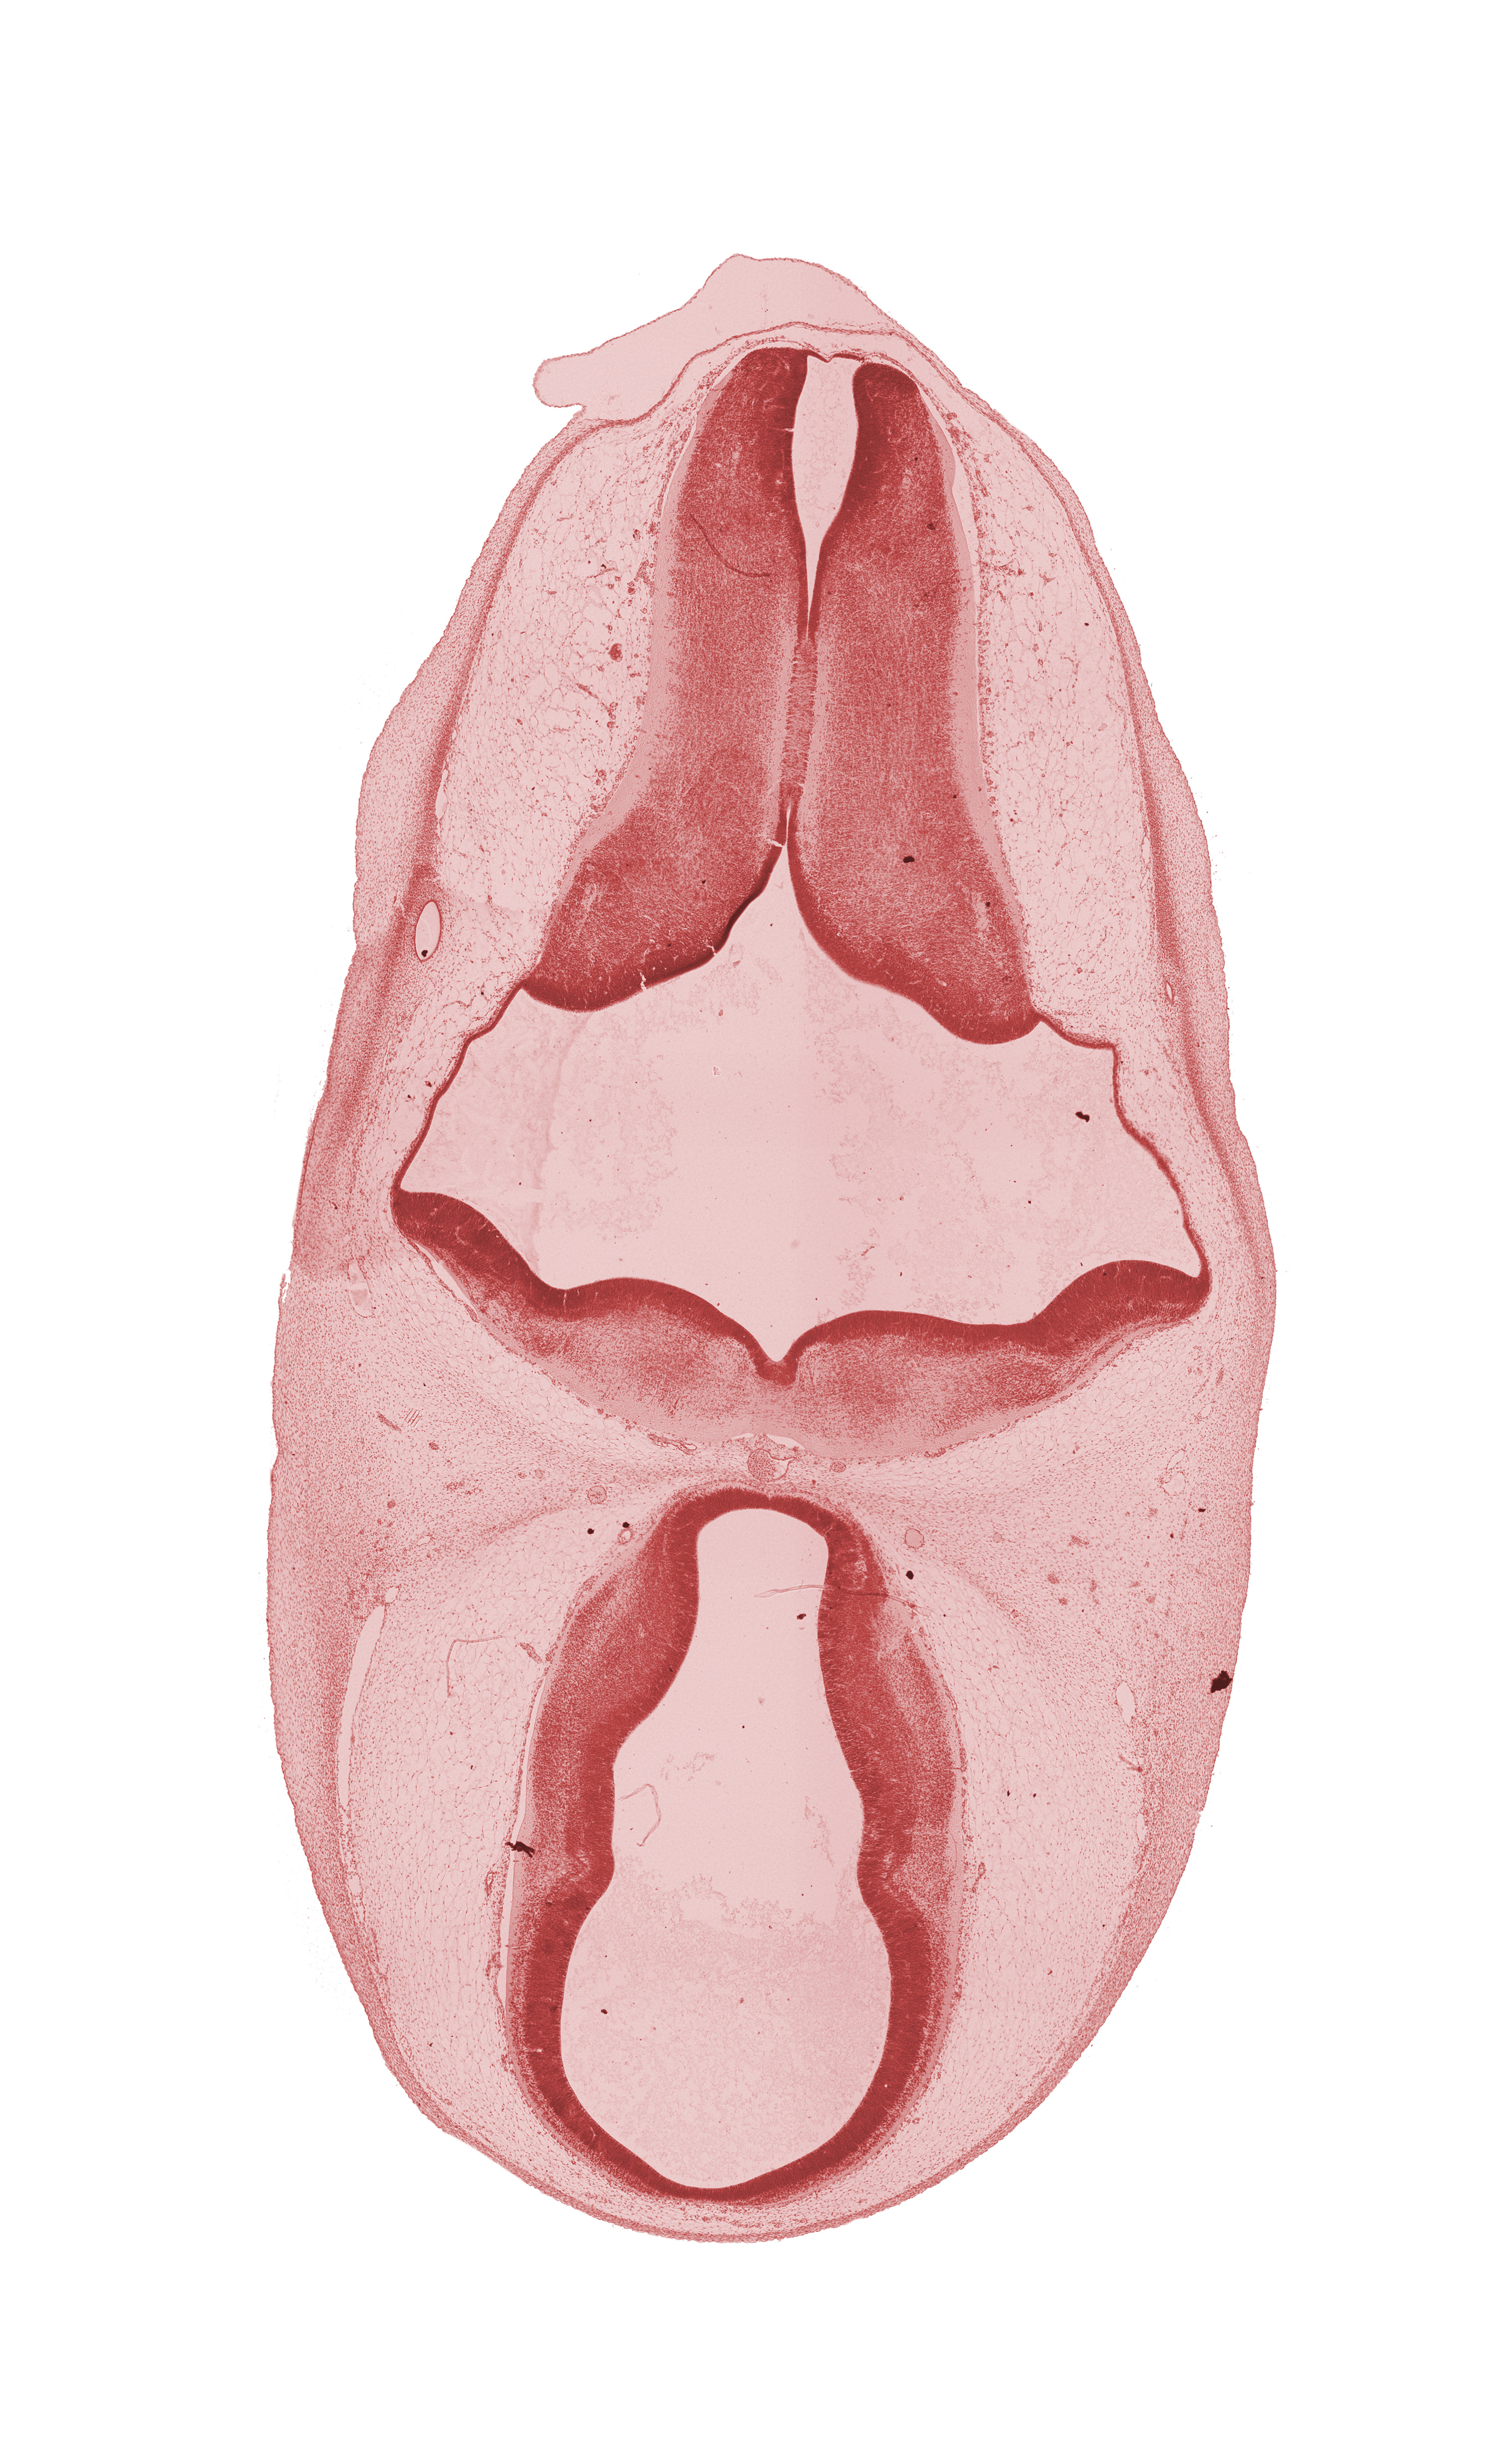

Carnegie Embryo #4430   |   Location: 7-15

Keywords: dorsal sulcus, dorsal thalamus, endolymphatic duct, epithalamus, hypothalamus, marginal ridge, osteogenic layer, rhombencoel (fourth ventricle), subarachnoid space, third ventricle, ventral thalamus